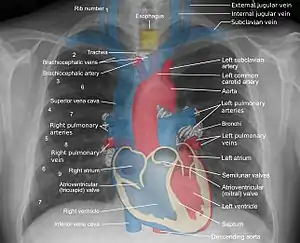

Landmarks

In the average person, the diaphragm should be intersected by the 5th to 7th anterior ribs at the mid-clavicular line, and 9 to 10 posterior ribs should be viewable on a normal PA inspiratory film. An increase in the number of viewable ribs implies hyperinflation, as can occur, for example, with obstructive lung disease or foreign body aspiration. A decrease implies hypoventilation, as can occur with restrictive lung disease, pleural effusions or atelectasis. Underexpansion can also cause interstitial markings due to parenchymal crowding, which can mimic the appearance of interstitial lung disease. Enlargement of the right descending pulmonary artery can indirectly reflect changes of pulmonary hypertension, with a size greater than 16 mm abnormal in men and 15 mm in women.[6]

Appropriate penetration of the film can be assessed by faint visualization of the thoracic spines and lung markings behind the heart. The right diaphragm is usually higher than the left, with the liver being situated beneath it in the abdomen. The minor fissure can sometimes be seen on the right as a thin horizontal line at the level of the fifth or sixth rib. Splaying of the carina can also suggest a tumor or process in the middle mediastinum or enlargement of the left atrium, with a normal angle of approximately 60 degrees. The right paratracheal stripe is also important to assess, as it can reflect a process in the posterior mediastinum, in particular the spine or paraspinal soft tissues; normally it should measure 3 mm or less. The left paratracheal stripe is more variable and only seen in 25% of normal patients on posteroanterior views.[7]

Localization of lesions or inflammatory and infectious processes can be difficult to discern on chest radiograph, but can be inferenced by silhouetting and the hilum overlay sign with adjacent structures. If either hemidiaphragm is blurred, for example, this suggests the lesion to be from the corresponding lower lobe. If the right heart border is blurred, than the pathology is likely in the right middle lobe, though a cavum deformity can also blur the right heard border due to indentation of the adjacent sternum. If the left heart border is blurred, this implies a process at the lingula.[8]